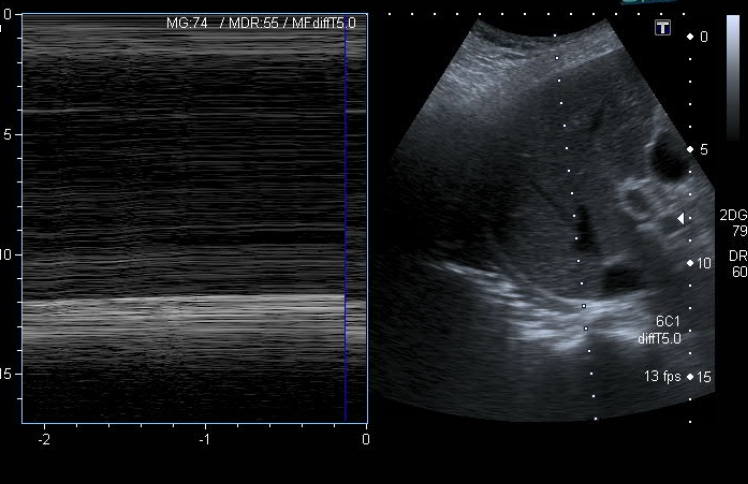

Ecografía diafragmática: se identifica una marcada elevación del hemidiafragma derecho, que se encuentra aplanado con los movimientos respiratorios (imagen 3 y 4) en modo M, compatible con parálisis diafragmática. No se visualiza líquido en fosa de Morrison. El hemidiafragma izquierdo se encuentra normoposicionado con movimientos normales y acordes a la respiración.